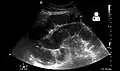

- Small bowel obstruction on ultrasound.[15]

Small bowel obstruction on ultrasound.[15]

Radiological signs of bowel obstruction include bowel distension and the presence of multiple (more than six) gas-fluid levels on supine and erect abdominal radiographs. Ultrasounds may be as useful as CT scanning to make the diagnosis.[13]